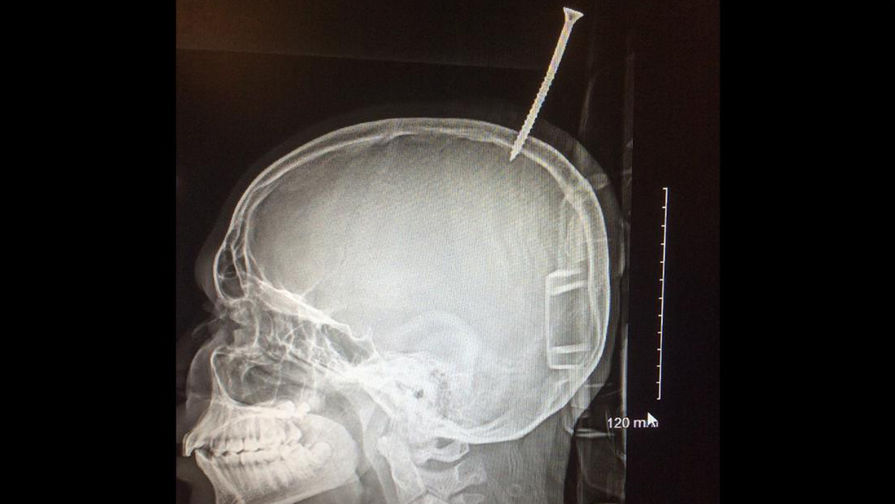

Нейрохирурги в США извлекли из черепа ребенка 15-сантиметровый шуруп

Нейрохирурги в США извлекли из черепа ребенка 15-сантиметровый шуруп — на голову мальчика свалилась доска. Врачи отмечают, что если бы шуруп отклонился хотя бы на миллиметр, мальчик бы погиб от кровотечения.

Семиклассник из США чудом выжил после того, как его голову пронзил 15-сантиметровый шуруп, вошедший в мозг. О необычном случае нейрохирурги рассказали каналу CNN.

13-летний Дариус Форман помогал двоюродным братьям строить дом на дереве, когда сорвался с ветки и упал на землю. Вслед за ним полетела и полутораметровая доска с 15-сантиметровым шурупом.

Когда мальчик поднялся, оказалось, что шуруп вошел в череп, прикрепив доску к голове.

Тетя быстро уложила мальчика на землю и вызвала медиков. Но даже они не сразу поняли, в каком опасном положении оказался Дариус. Шуруп не только повредил его череп, но и вошел в мозг в области верхнего саггитального синуса, крупной вены, расположенной между полушариями мозга и направляющими кровь от него к сердцу. Если бы шуруп пронзил вену, мальчик бы погиб от кровоизлияния.

«Еще бы миллиметр — и он бы истек кровью», — отмечает нейрохирург Алан Коэн.

После рентгена было решено отправить мальчика для операции в больницу Джонса Хопкинса в Балтиморе. Медикам пришлось одолжить вертолет у полиции — больничный оказался недостаточно большим.

Наконец, врачи приступили к операции. Нейрохирург Шенадоа Робинсон избавилась от остатков доски и верхней части шурупа.

К счастью, спустя семь часов после получения травмы врачи смогли извлечь остатки шурупа вместе с небольшими осколками черепа и сгустками крови, образовавшимися в области травмы.

По словам врачей, они проделали практически ювелирную работу. Им пришлось рассверлить череп вокруг шурупа.

«Если бы мы попытались выкрутить его, это могло привести к обильному кровотечению, — объясяет Коэн.— Мы тщательно просверлили кость до мозговой оболочки, чтобы добраться до шурупа».

На место удаленного фрагмента черепа врачи установили титановую пластинку. А остатки шурупа они подарили Дариусу — на память о его несостоявшемся знакомстве со смертью. Он был выписан из больницы в свой 13-й день рождения.